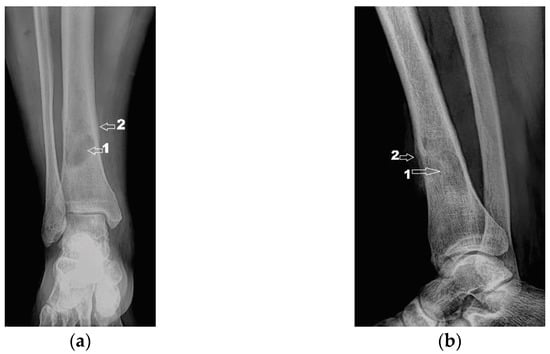

The subsequent evolution was favorable, 6 months after the surgery the patient no longer having local pain. The radiological examination showed a favorable local evolution, without signs of tumor recurrence (Figure 12). Furthermore, the patient did not show any other specific symptoms of RDD, which is why no systemic treatment (glucocorticoids or other immunomodulatory drugs) was initiated.

Figure 12. Radiological 6-month follow-up: (a) coronal view; (b) lateral view.